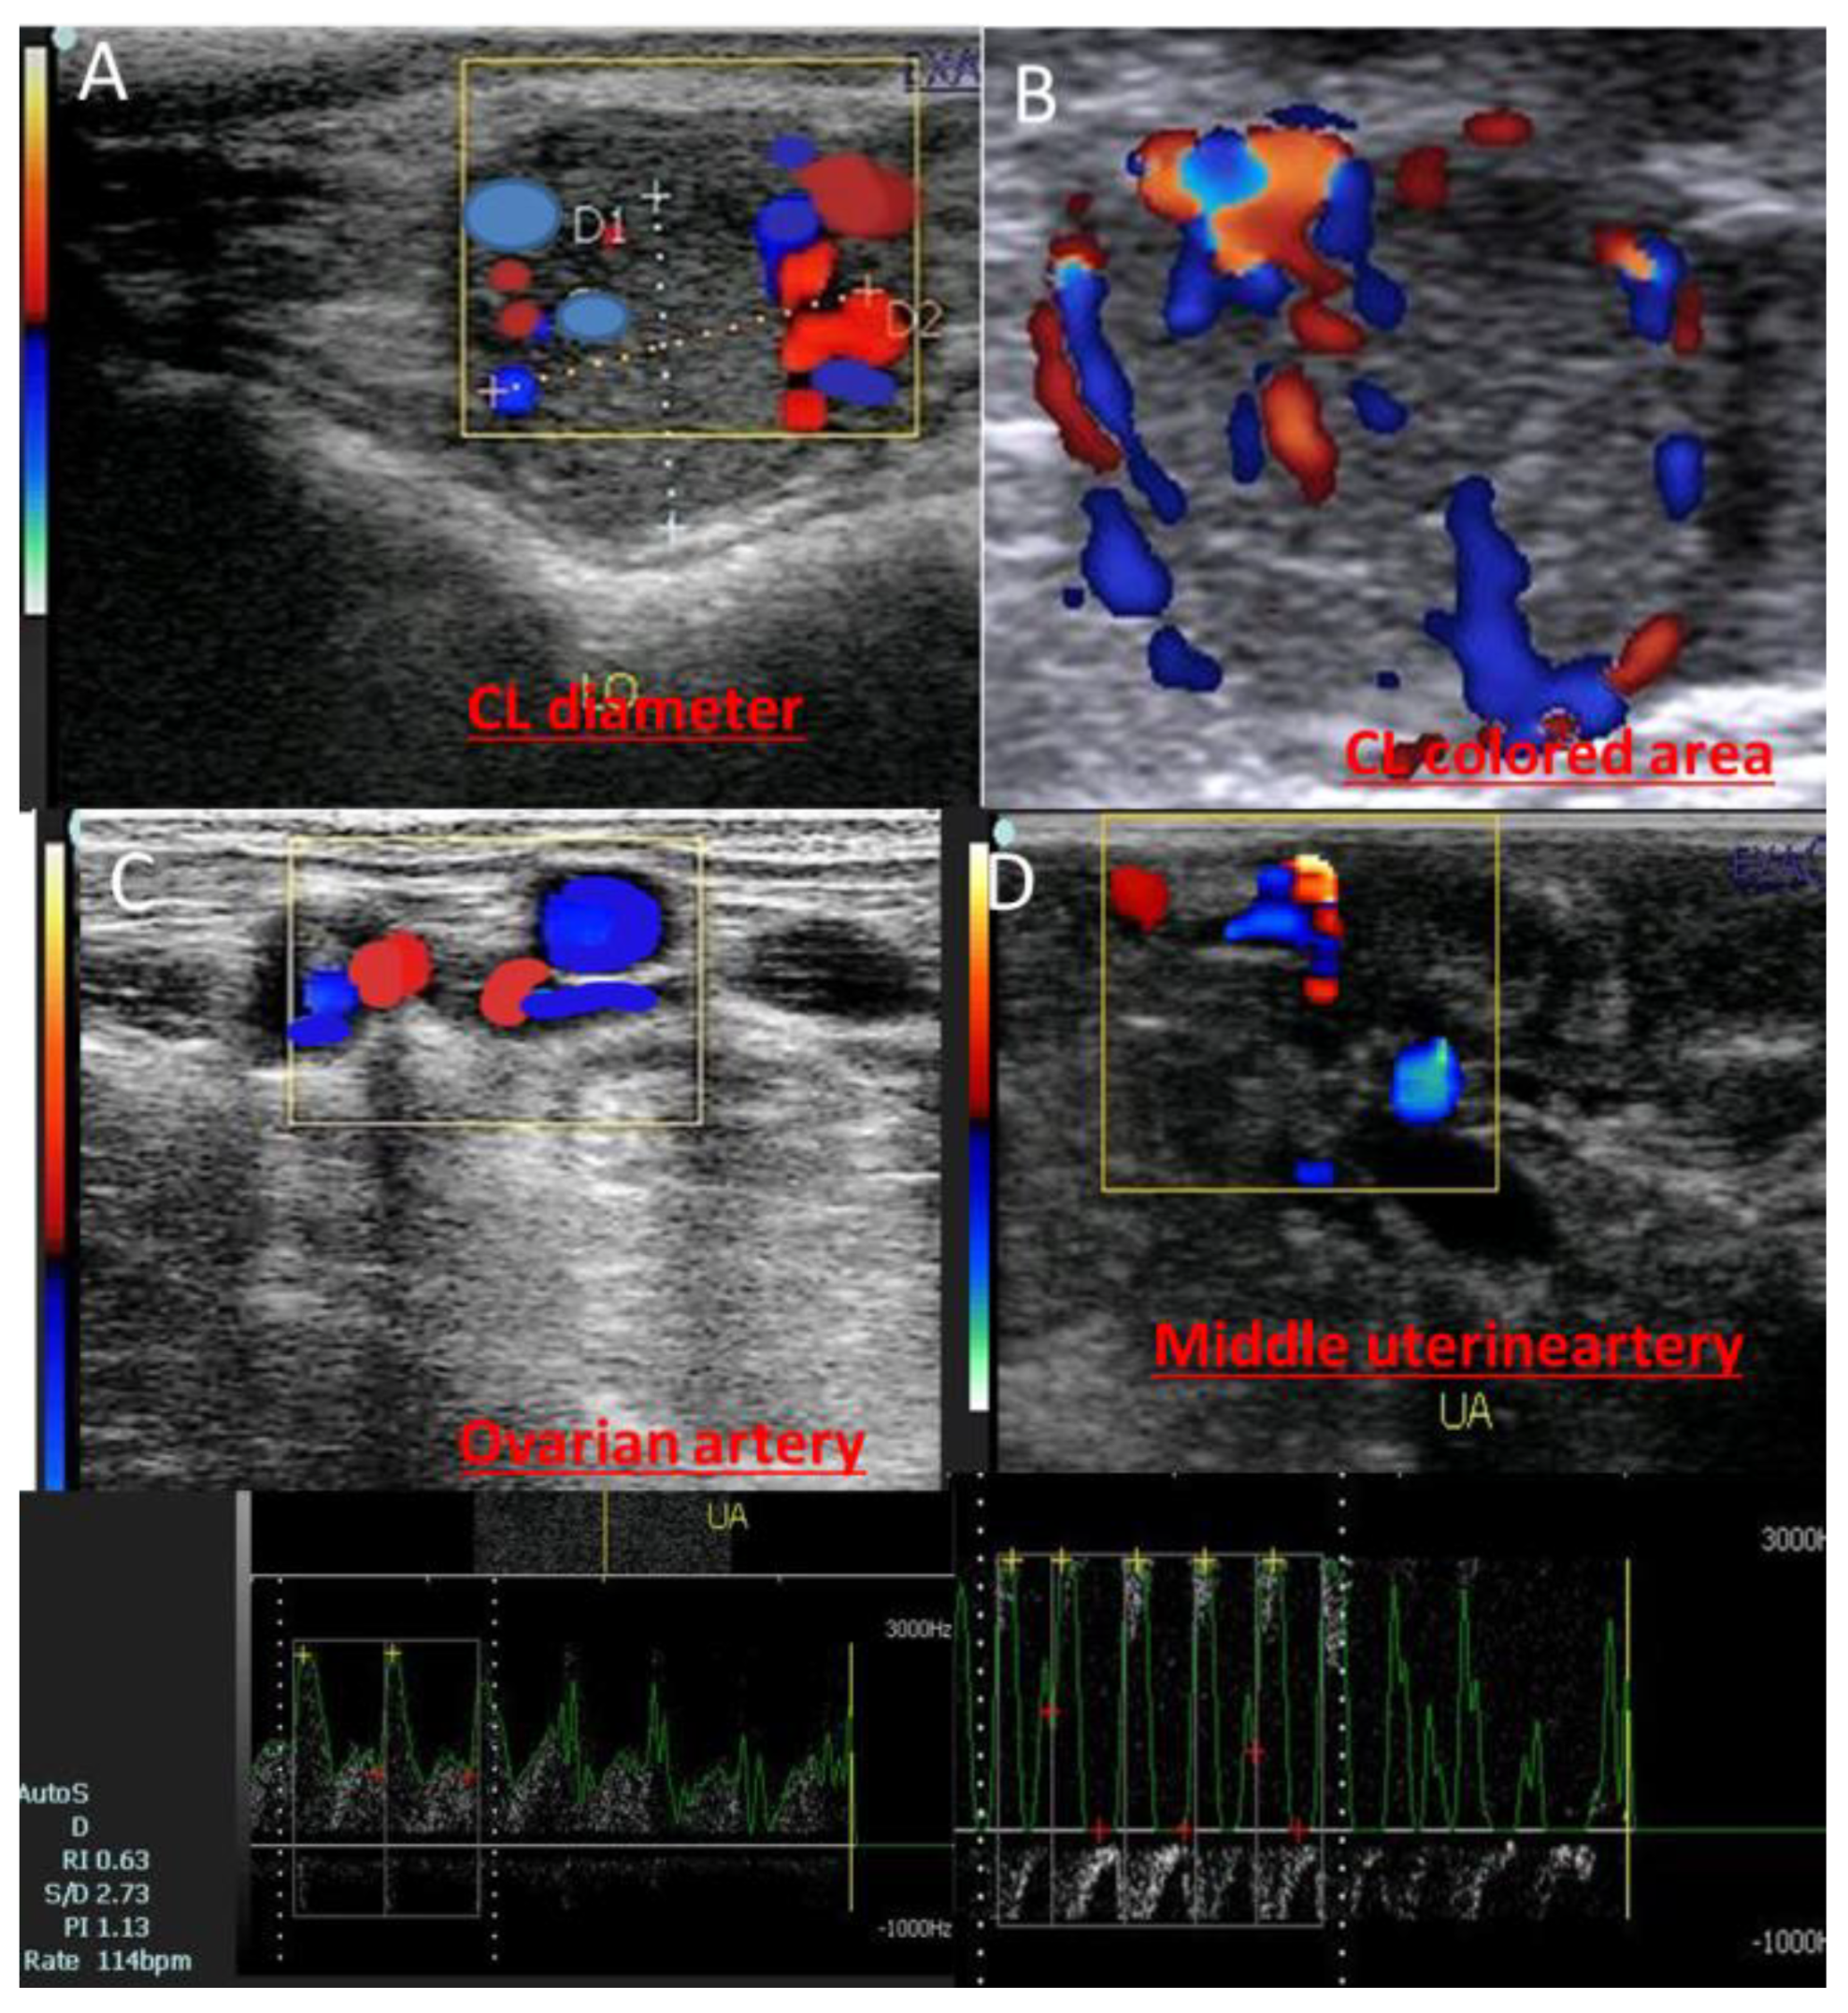

2.3. B- and Color Modes for Luteal Changes and Uteroovarian Vascular Perfusion

2.4. Data and Image Analysis